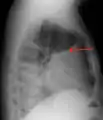

A pleural effusion appears as an area of whiteness on a standard posteroanterior chest X-ray.[12] Normally, the space between the visceral pleura and the parietal pleura cannot be seen. A pleural effusion infiltrates the space between these layers. Because the pleural effusion has a density similar to water, it can be seen on radiographs. Since the effusion has greater density than the rest of the lung, it gravitates towards the lower portions of the pleural cavity. The pleural effusion behaves according to basic fluid dynamics, conforming to the shape of pleural space, which is determined by the lung and chest wall. If the pleural space contains both air and fluid, then an air-fluid level that is horizontal will be present, instead of conforming to the lung space.[13] Chest radiographs in the lateral decubitus position (with the patient lying on the side of the pleural effusion) are more sensitive and can detect as little as 50 mL of fluid. Between 250 and 600mL of fluid must be present before upright chest X-rays can detect a pleural effusion (e.g., blunted costophrenic angles).[14]

A pleural effusion as seen on lateral upright chest x-ray- Pleural effusion as seen behind the heart.[17]